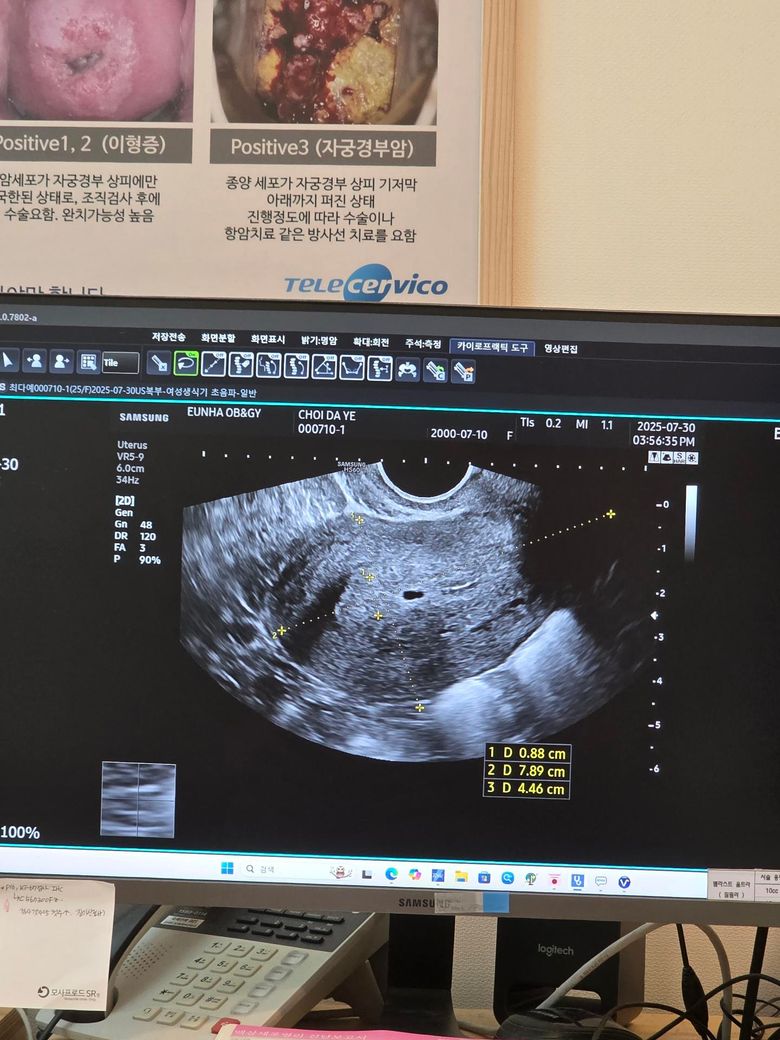

초음파 봤는데 기포 라고 생리유도 주사 맞았습니다 한번 봐주세요

초음파에서 자궁 내 약 0.88cm 크기의 검은 구조물이 발견되었습니다.

담당 의사님은 임신은 아니라고 하시며 (β-hCG 피검사 수치 0.2 미만),

그 구조물은 기포처럼 보여서 주사로 빼자고 하셨습니다

참고로 초음파 사진도 첨부합니다.

• 1번 째 사진